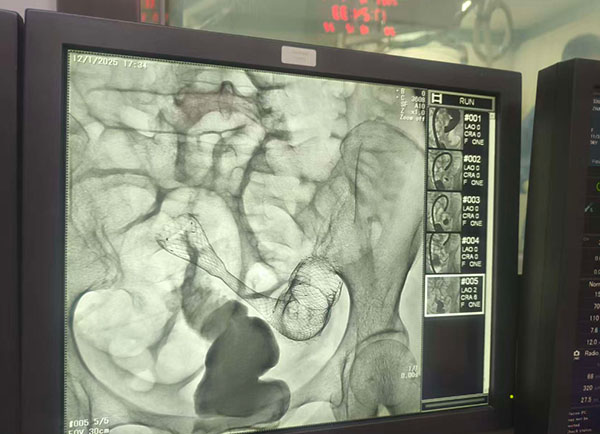

▲放消化道支架 解除肠梗阻

我院消化内科团队率先出击,联合影像科,紧急进行了肠镜检查并顺利置入肠道支架,缓解肠梗阻的同时,老人的胃肠功能逐步恢复,开始肠外肠内营养治疗。随后,在医务部协调下,组织了一场高规格的多学科联合诊疗,麻醉科、呼吸与危重症医学科、心血管内科、肾内二科以及重症医学科专家们齐聚一堂,共同评估风险,优化诊治流程。